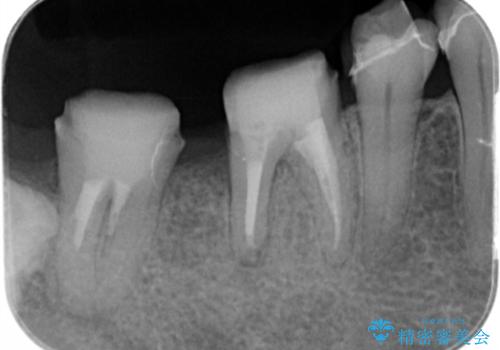

1年間他の治療を行いながら待ったのち、骨の状態確認を行う確定外科の際にしっかりと骨の再生が認められました。